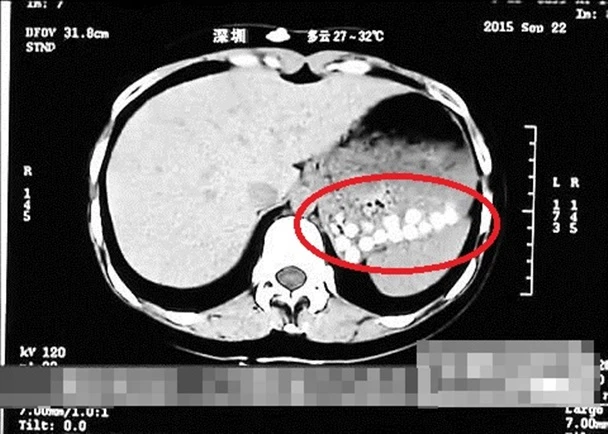

Trong chương trình thường thức đời sống của đài này, một PV tại Thanh Đảo đã uống trà sữa trân châu mua tại một cửa hàng địa phương sau đó chụp CT phần ổ bụng tại bệnh viện gần đó. Bản chụp CT cho thấy những hạt trân châu này không tiêu hóa được và nằm dồn lại trong dạ dày.

Các hạt trân châu nằm lại trong ổ bụng. (Nguồn: Đài truyền hình Sơn Đông)